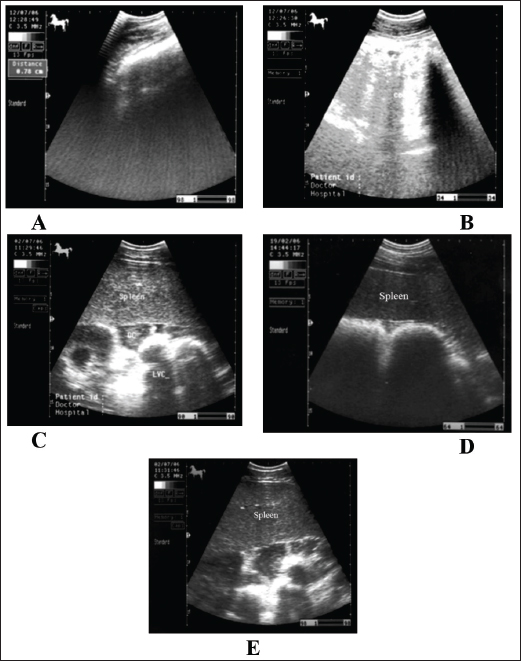

Fig. 5. Ultrasonogram of the cecum, left ventral colon (LVC), and right ventral colon (RVC) in 4 horses with flatulent colic. In A, the cecal wall appears echogenic in the absence of sacculations. In B, the LVC shows an echogenic wall with no sacculations. In C, the RVC shows a thin wall that appears echogenic in the absence of sacculations. In D, RVC appears in the absence of sacculations and with increased wall thickness. These organs contain a large amount of gas, which hinders their visualization.

The cecum of horses with flatulent colic appears thin-walled due to gas distension; absence of sacculations; hypomotility on real-time ultrasonography, and the gases in the cecum prevent visualization of the ingesta inside the cecum (Le Jeune and Whitcomb, 2014). In comparison to healthy horses, the cecum is identified by its sacculations and contractions. The left ventral colon appears with a thin echogenic wall, the absence of sacculations, and the gases inside hinder the visualization of the ingesta. The right ventral colon compared to clinically normal horses shows the absence of sacculations and might be with thin or increased wall thickness, and this agrees well with Scharner et al., (2002), while in control horses it is characterized by the presence of sacculations, bright hyperechoic line, and the inability to identify the entire circumference of its wall (Fig. 5). Horses suffering from severe gas accumulation may collapse where postmortem examination confirms the diagnosis (Tharwat et al., 2008).

In flatulent colic, temperature and respiration are elevated, the pulse rarely exceeds 70 beats /minute, and the mucous membrane is pale. Rectal examination revealed gas-filled portions of the intestines, and distended portions of the jejunum or ileum could be felt as thin-walled loops without sacculations and taeniae. Auscultation of the abdomen revealed decreased peristalsis but not totally absent. In addition, stomach distension may occur resulting in severe signs of pain, sweating, pawing, and hyperactivity (Worku et al., 2017). Horses with flatulent colic usually appear bloated, especially in the right flank, and show signs of severe pain, which may be intermittent or constant with particularly painful spasms. Auscultate pinging sounds are present over the right dorsal flank and midabdominal area (Beccati et al., 2011). The main diagnostic techniques for the tympanic colic in equines are radiography and sonography. Ultrasonographically, Tharwat et al., (2008) reported that flatulent colic bowel appeared distended with gas that prevented visualization of the ingesta inside, and the sacculations disappeared. The peristaltic activity of the gas-distended segment is decreased or absent (Tharwat et al., 2008).